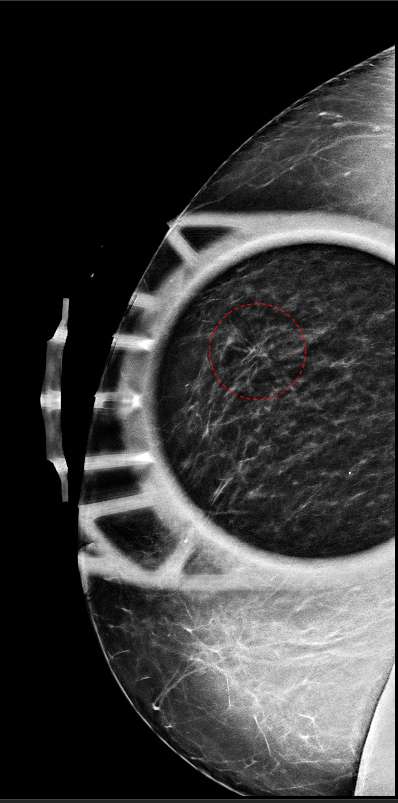

Figure 2 shows spot compression tomosynthesis of the architectural distortion shown in Figure 1. Note how the region of architectural distortion does not appear to “smooth out”, but rather retains a fairly stable appearance compared to Figure 1.